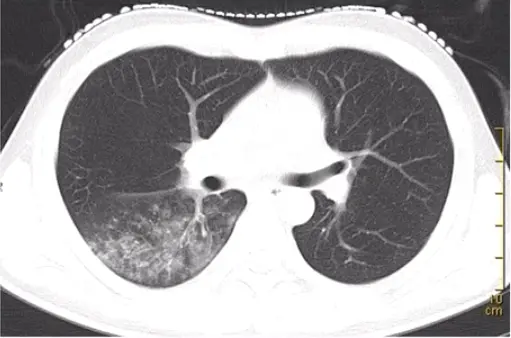

第三题:如下图所示,病变表现为双肺多发斑片、磨玻璃影。可见小叶中心结节、树芽征。

第三题答案:金黄色葡萄球菌肺炎,常表现为小叶性肺炎。